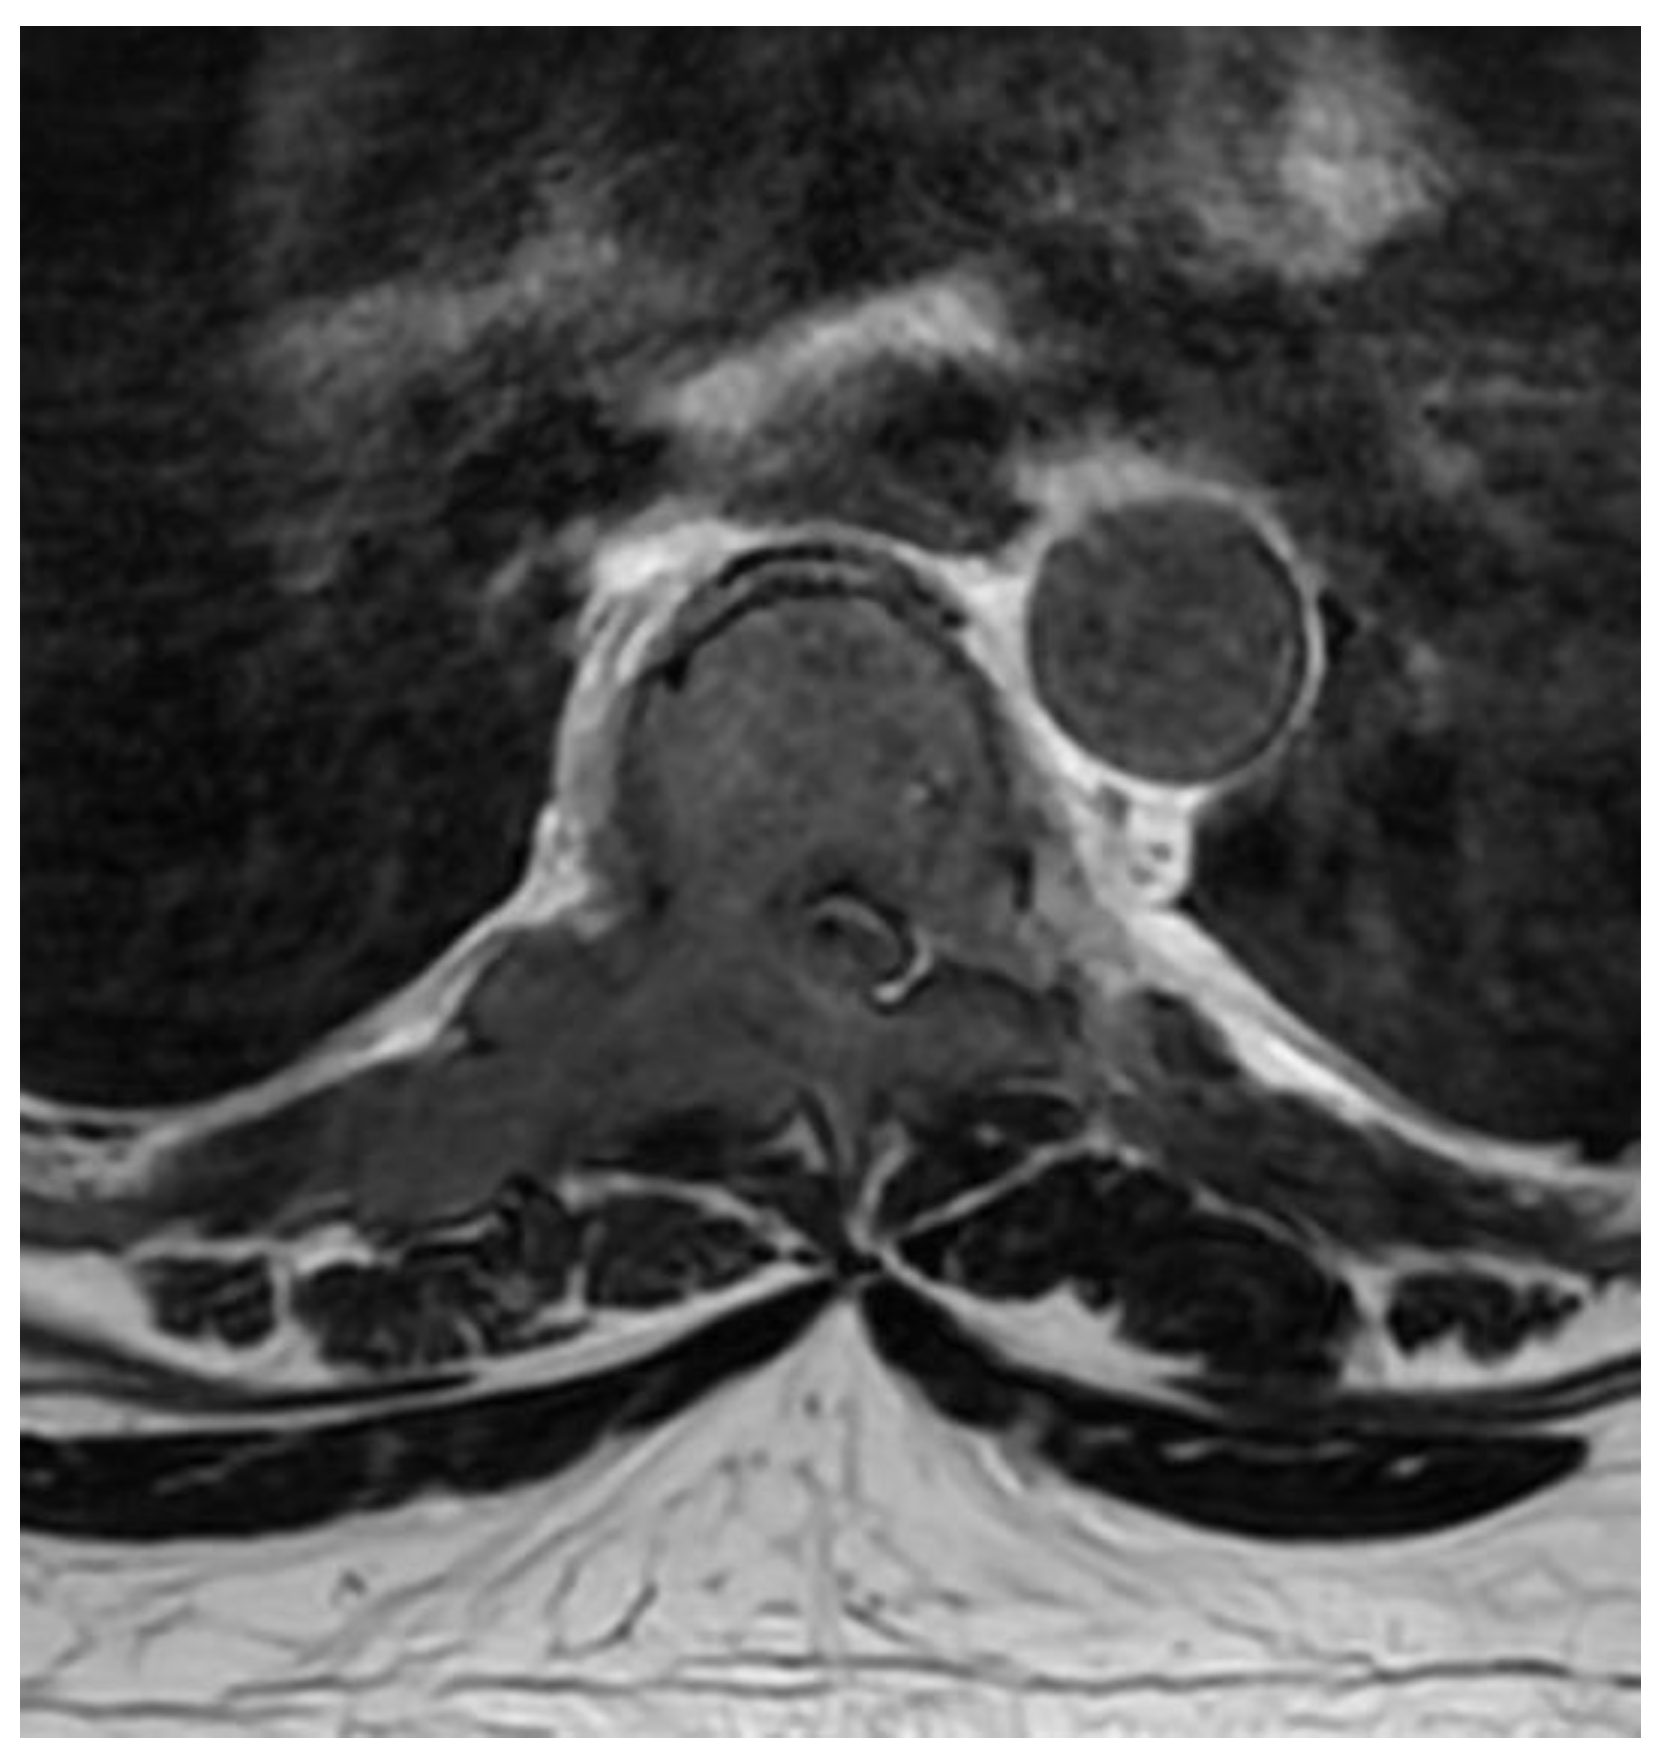

Fully Endoscopic Spine Separation Surgery in Metastatic Disease—Case Series, Technical Notes, and Preliminary Findings

3. Results